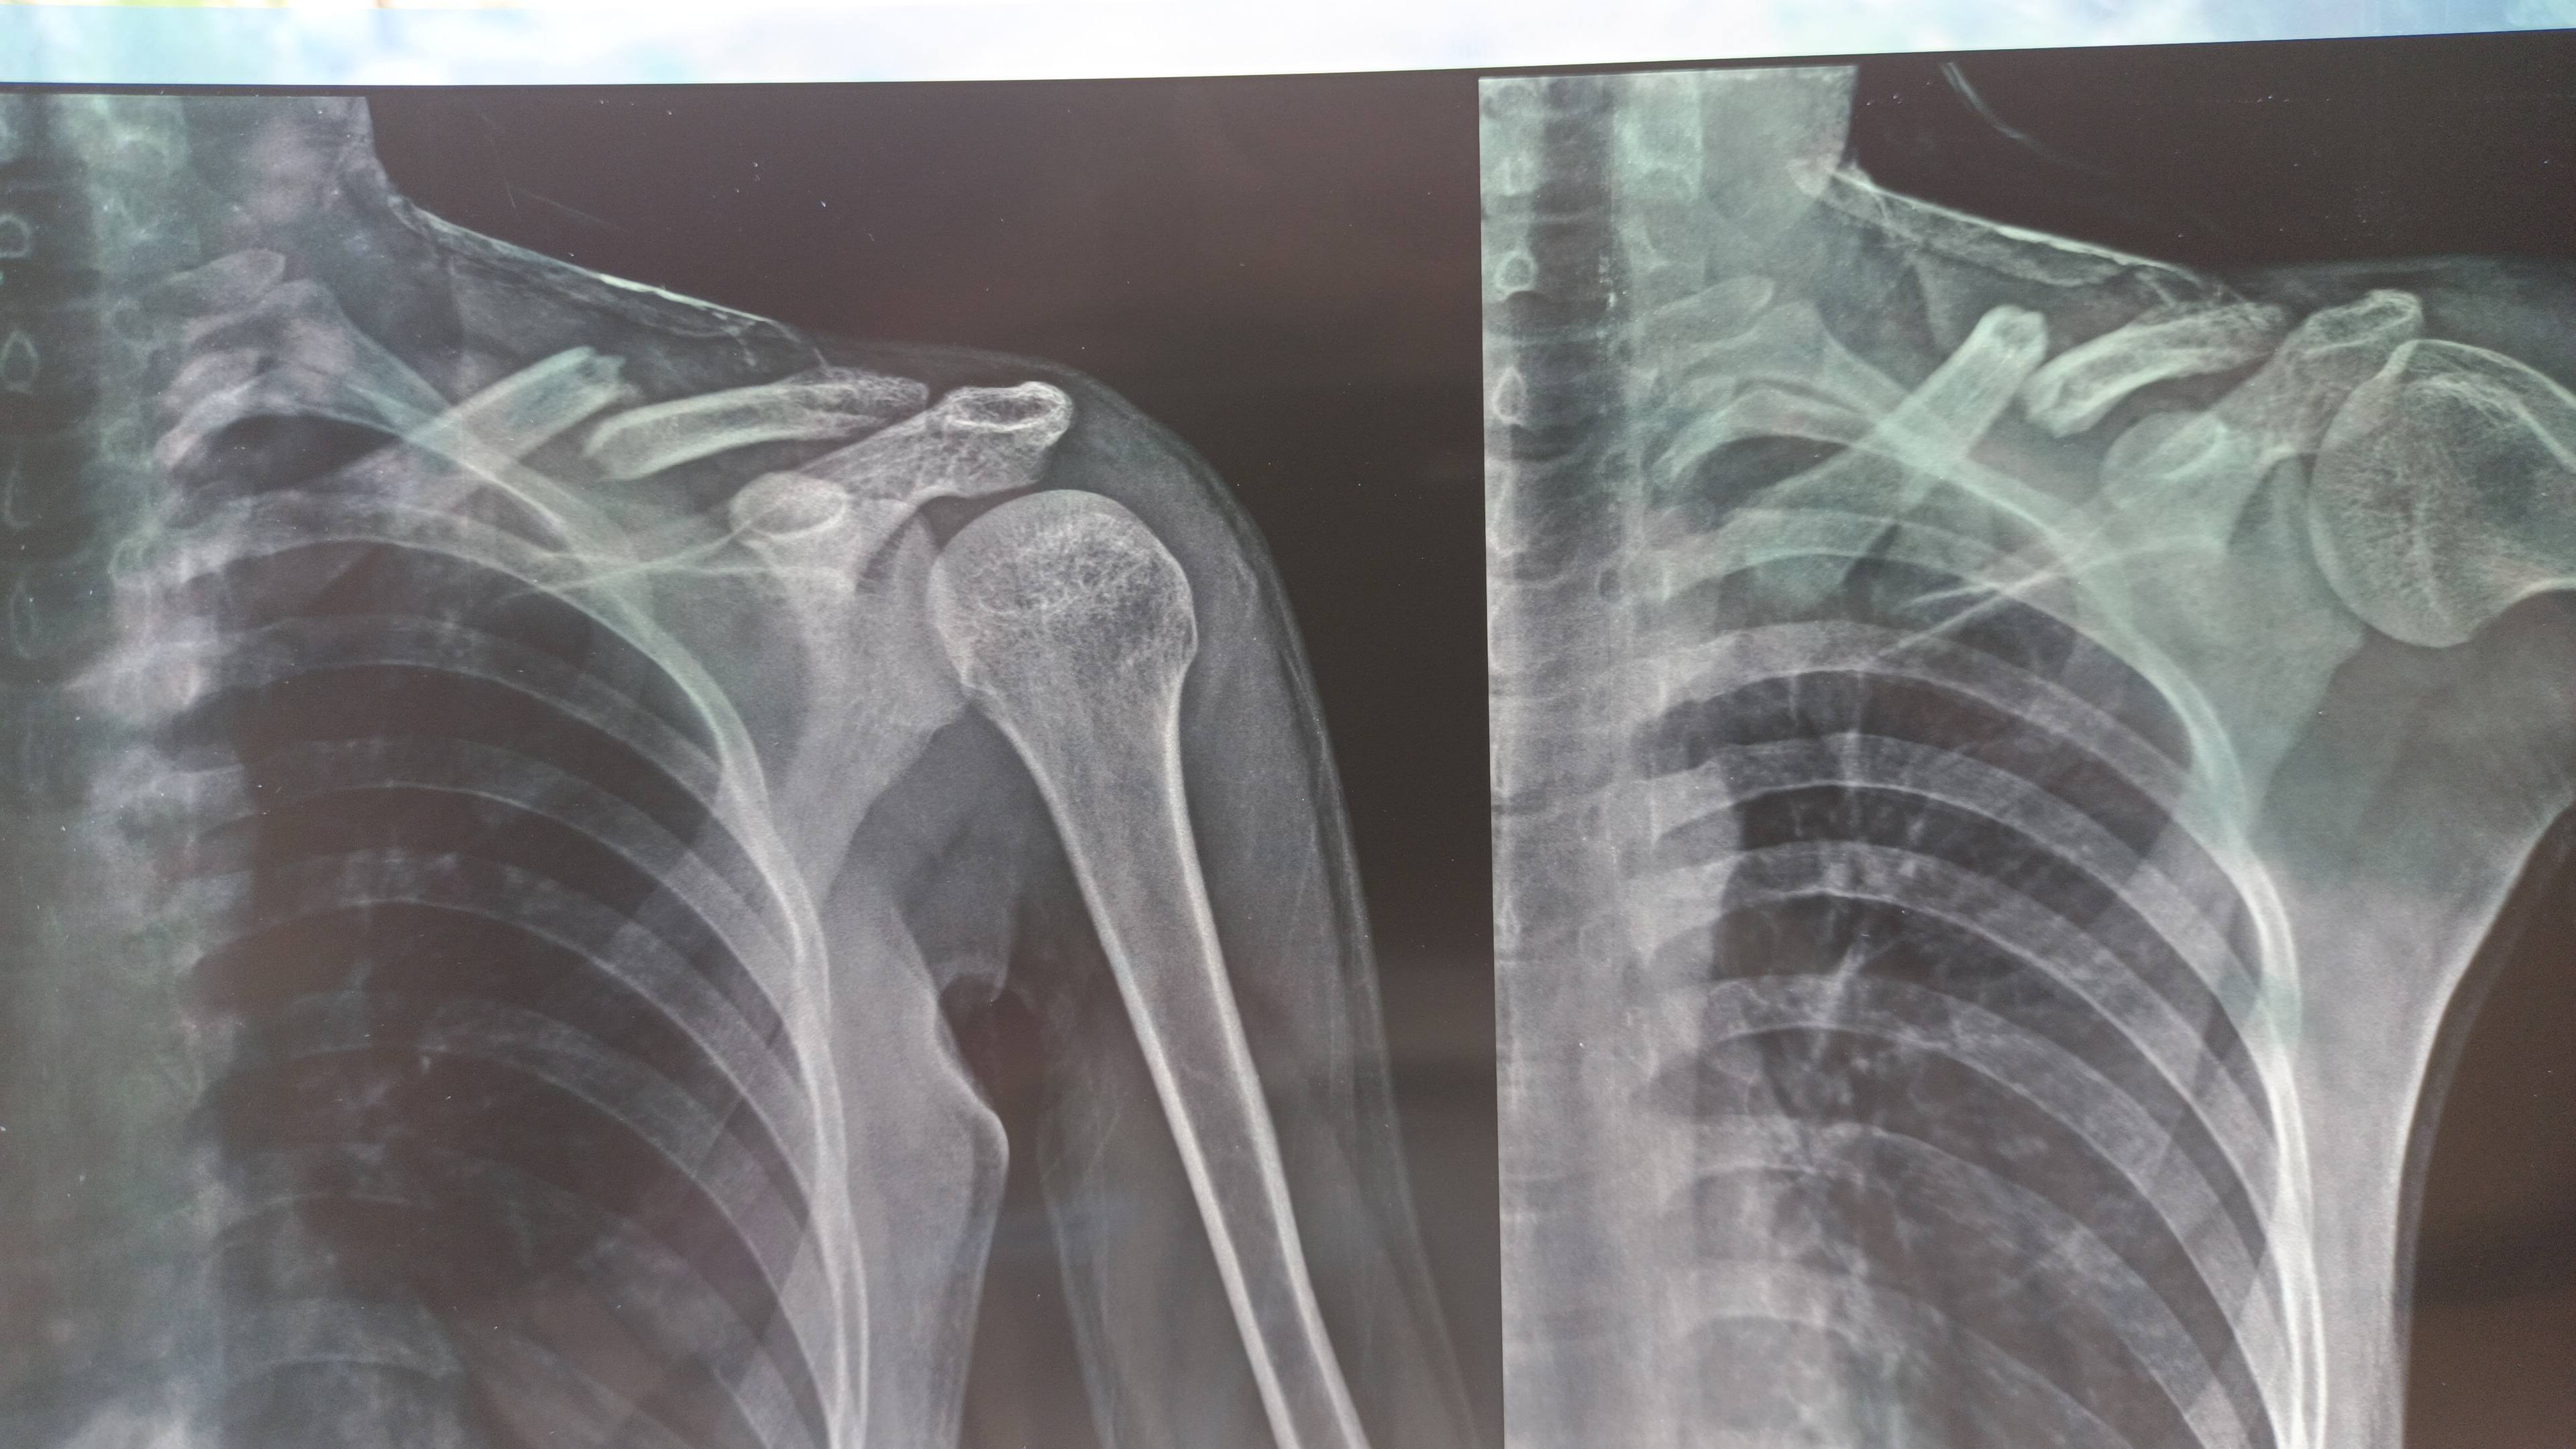

Name: Yubaraj Pandey

Yubaraj Pandey

I have pain in my left shoulder Can you find out what's the problem ?

Here are x-rays of 2 different dates and inform me after complete

reason of accident (Fallen From Tree)